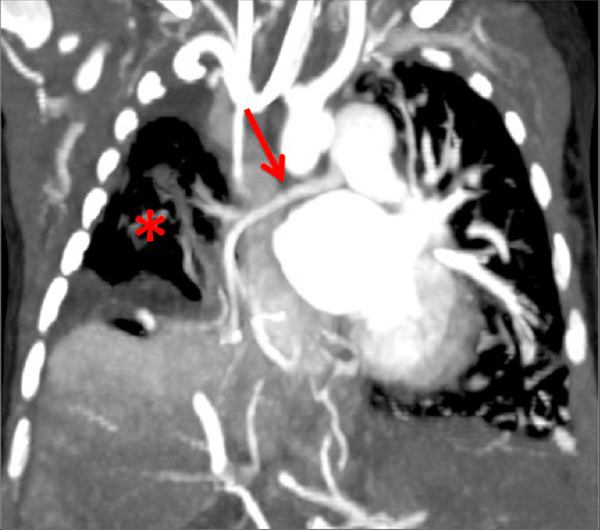

Figure 7

Portopulmonary hypertension in a 16-year-old. No abnormalities were found on morphological computed tomography (A/B), but heterogeneous perfusions were present on the perfusion map (stars, C/D).